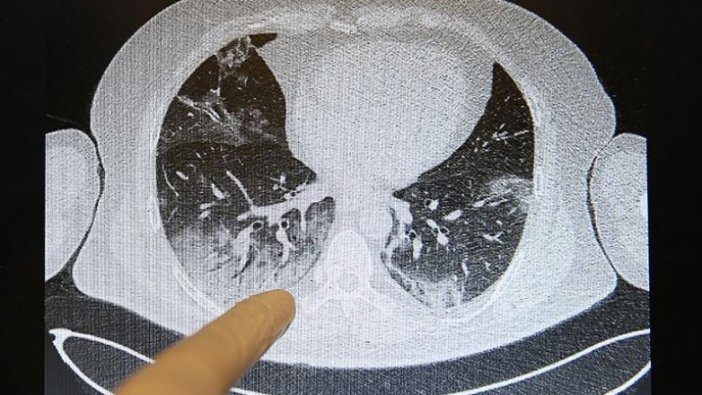

İşte Kovid-19'un akciğerlere verdiği zarar